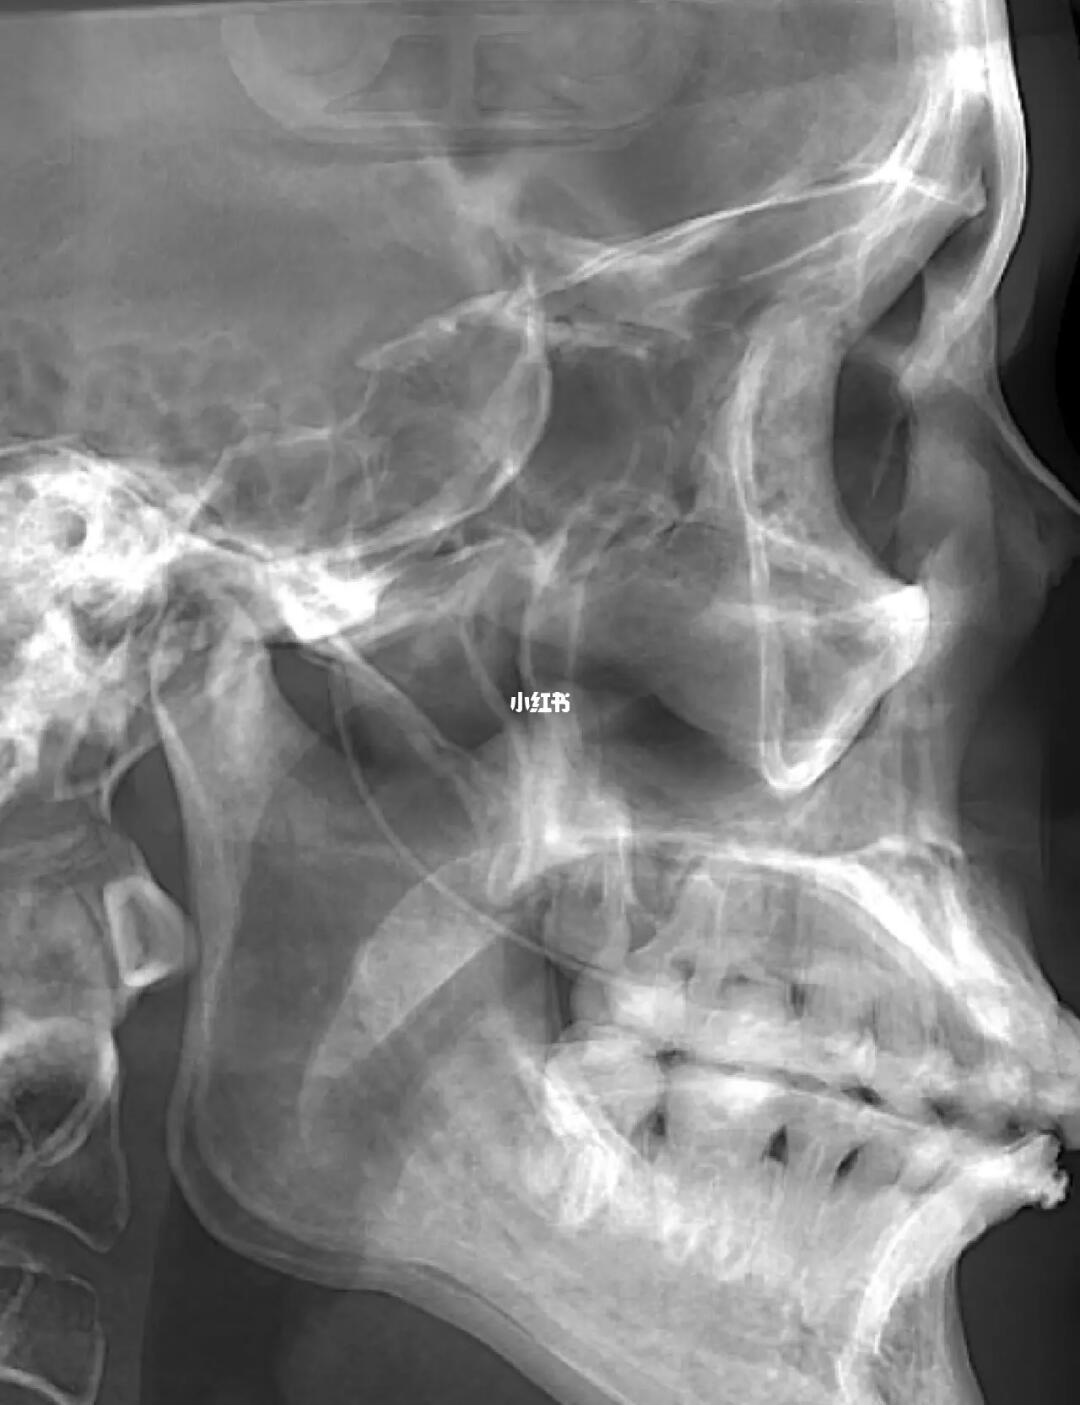

[惊恐R]通过拍片发现,上颌牙的正畸钢丝越过翼静脉丛都快插进颅内了[惊恐R]都靠近脑膜中动脉了,这要是再深一点或者偏一些[惊恐R]刺破了血管,后果不堪设想!